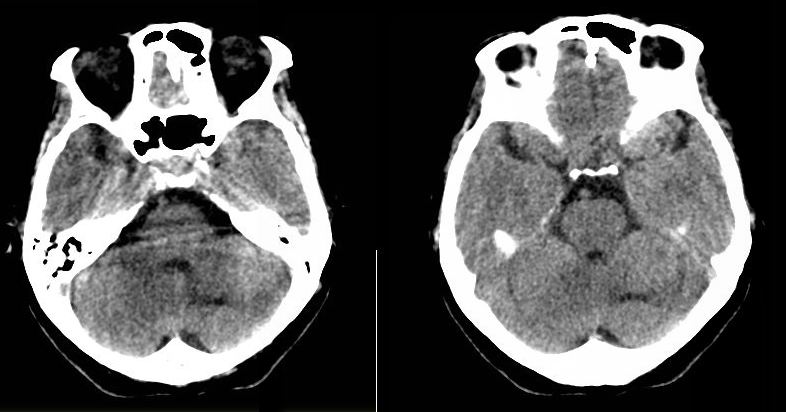

病人资料:女,57岁,反复头痛6年余,无恶心、呕吐等症状,体查:bp180/100mmhg。

胼胝体发育不良半脂肪瘤 松果体钙斑增大 原因?

胼胝体发育不良并脂肪瘤形成,脂肪瘤形成是因,胼胝体发育不良是果。如果正规些应该是中线脂肪瘤并胼胝体发育不良!

典型中线脂肪瘤

胼胝体发育不良

中线脂肪瘤并胼胝体发育不良。